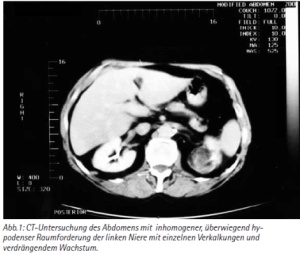

Ein 18-jähriger junger Mann stellte sich mit progredienter Hustensymptomatik in der Notaufnahme vor. Radiologisch fand sich bereits in der konventionellen Röntgenaufnahme eine unklare pulmonale Raumforderung, welche sich in der weiteren Abklärung histologisch als Tumor der Ewing-Sarkom-Familie herausstellte ohne weitere ossäre Beteiligung. Die weitere Therapie wird in einem Sarkomzentrum erfolgen.